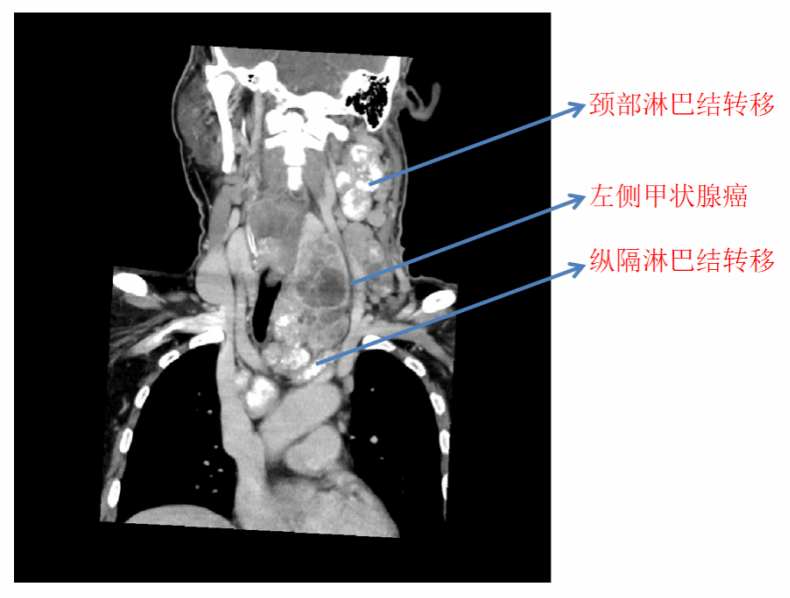

半年多前,57岁的老李在检查中发现了颈部肿物,但因肿物不痛不痒,老李便没有重视。近半年来,老李颈部的肿物越来越大,一家医院为他进行了左侧颈部肿物活检,结果显示为左侧高级别甲状腺髓样癌。PET-CT检查显示,老李颈部淋巴结广泛转移,纵隔淋巴结也未能幸免,疾病的恶性程度极高。老李先后去到多家医院,却都被告知没有好的解决办法,最后辗转来到北京大学第三医院。

患者颈部、纵隔淋巴结广泛转移